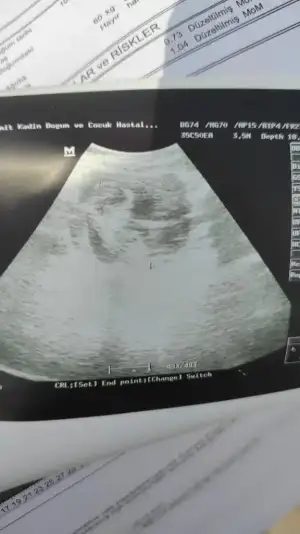

Cinsiyet tahmini yapan arkadaşlar bakabilir misiniz? Doktor %90 bir şey söyledi ama önceki doktor da başka bişey dediği için size sormak istiyorum. 12+6

• 717C05D4-FF20-40F5-BF95-6E7921F64DD5.webp

717C05D4-FF20-40F5-BF95-6E7921F64DD5.webp

22,8 KB · Görüntüleme: 74

• 7FFF74E7-E4F1-458C-AB66-9665D894BB84.webp

7FFF74E7-E4F1-458C-AB66-9665D894BB84.webp

37,1 KB · Görüntüleme: 76